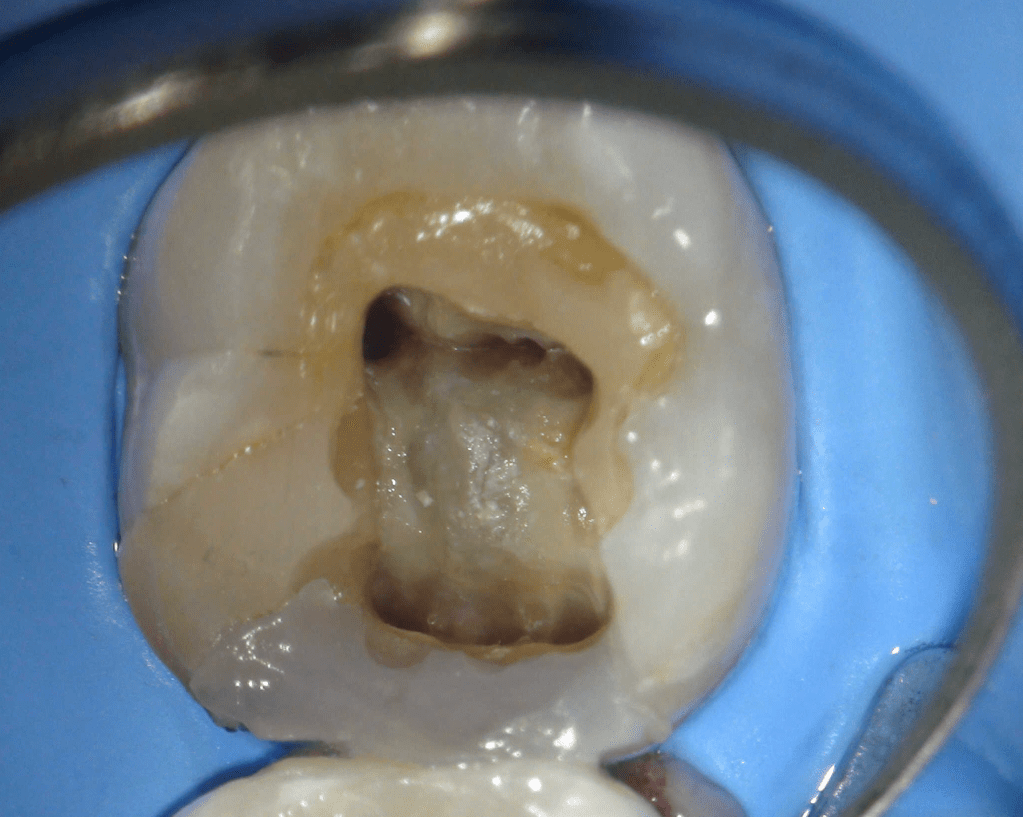

Pulpotomía biodentine + reco preendio